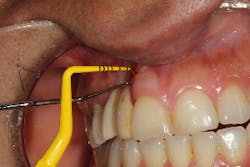

This patient presented with an unrestorable tooth No. 10 due to severe caries (figure 1). Prior to tooth extraction, the patient was informed that in order to avoid having a large defect, additional bone and soft-tissue grafting would be necessary. This type of augmentation would require additional time and finances, as well as increased surgical visits and appointments. The patient was informed that failure to undergo these procedures might result in (1) longer restorations, (2) the need for gingival ceramics, (3) inability to clean the prosthesis, and (4) increased forces on the implant because of the increased crown-to-implant ratio.

Tooth No. 10 was extracted. The socket was disinfected with chloramine-T gauze. An immediate implant (4.3 mm x 10 mm with a 5 mm healing screw) was placed (figure 2).